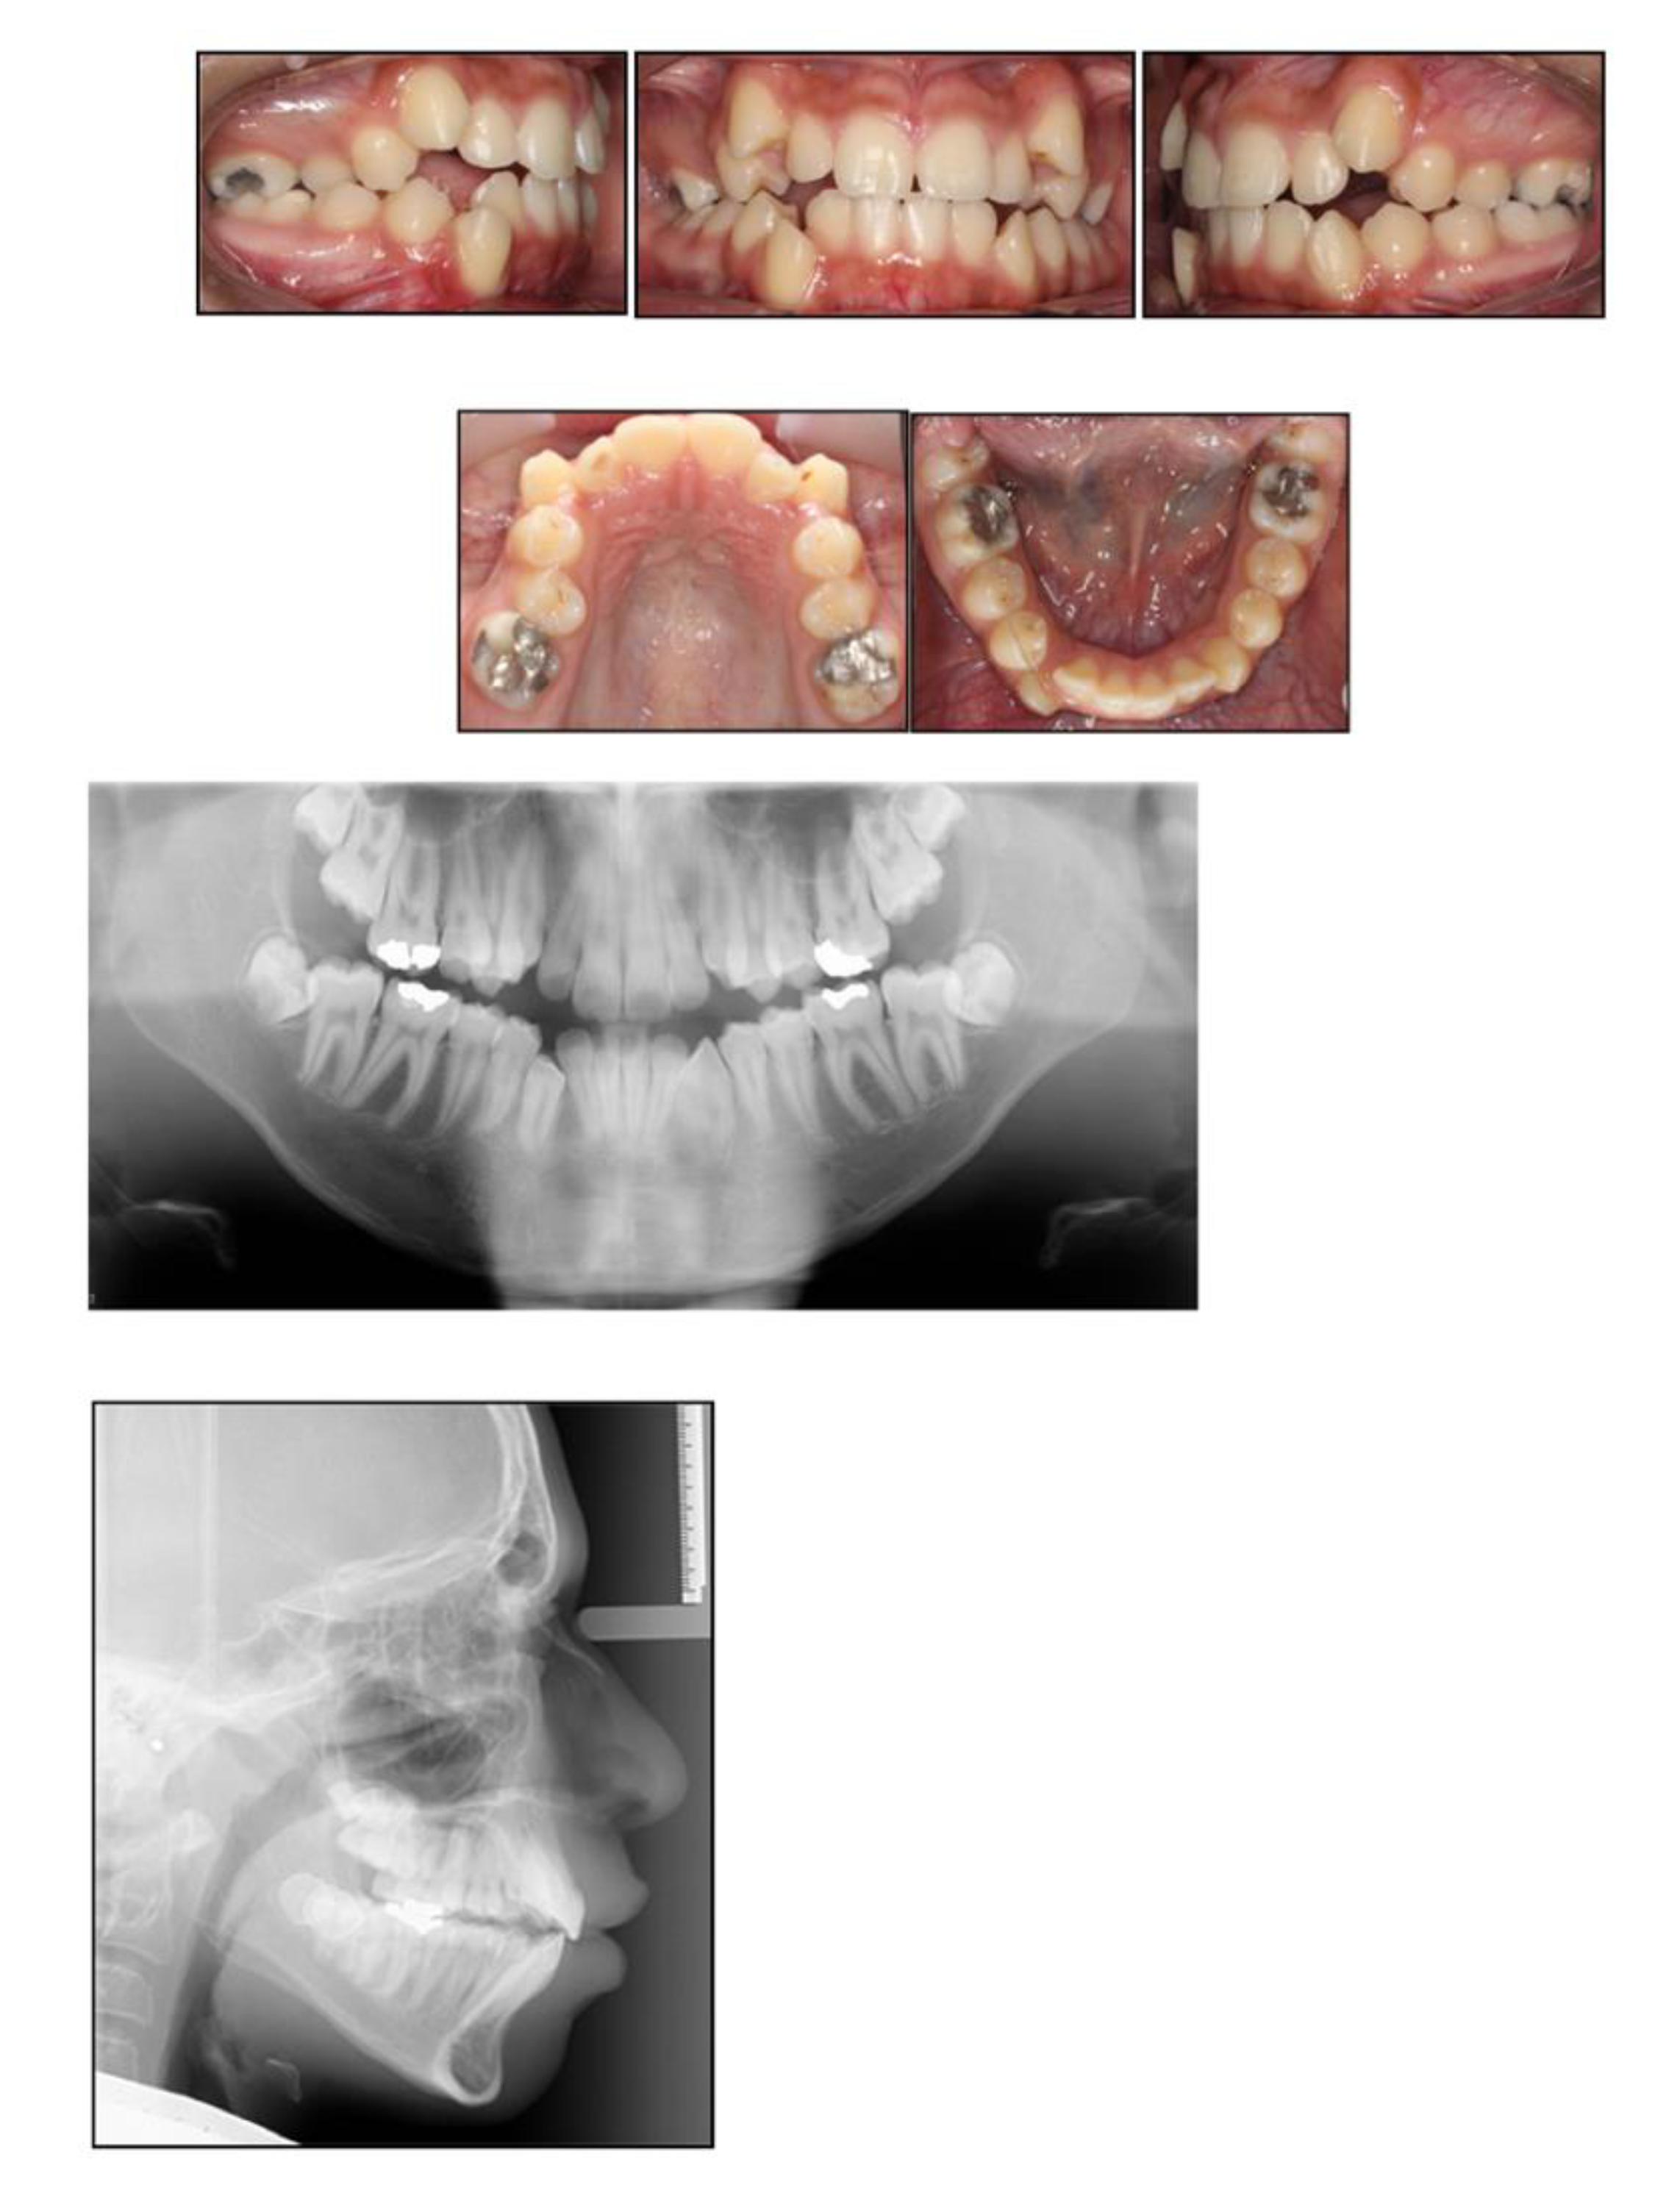

2.1. Case 1—Delayed Extraction of FPMs

Discussion

- ▪

- The upper second permanent molars were still within bone at the time of extraction;

- The OPT revealed signs of molar stacking of upper right and left second permanent molars, and distally tipped lower right and left second permanent molars reflecting posterior molar crowding;

- The distinct vertical growth pattern and presence of a steep mandibular plane, which encouraged molar mesial movement.